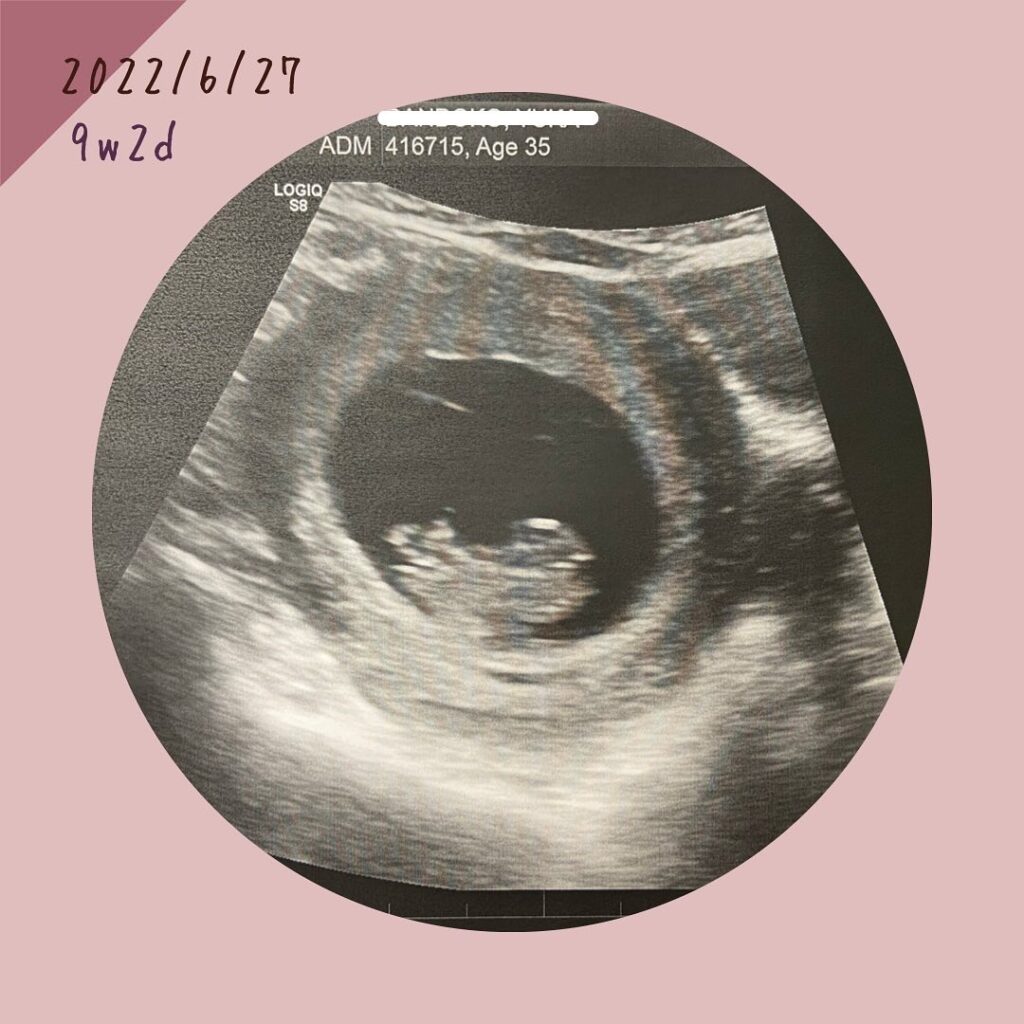

妊娠9週:初めてのエコー&心拍確認

妊娠3ヶ月で初エコー。

日本ではもっと早い段階でエコー見るよね??

カナダでの出産は保険適用内ということもあり、必要最低限の診察や治療をしないため、初めてエコーは流産の可能性が多いとされる妊娠早期をある程度過ぎた10週くらいからなのだそうです。

場所は、Victoria Dr.とE.41Ave.にあるウルトラサウンド(超音波)専門のラボでした。

妊娠発覚してから約1ヶ月半。

やっぱりこの目でお腹に赤ちゃんいるのを確認できないと、信じられないし、不安で不安で、初めてエコーで赤ちゃんと心拍を確認して、嬉しくて、ホッとして、大号泣でした😭

約1ヶ月半、ほんっとーーーに長く感じた!!!